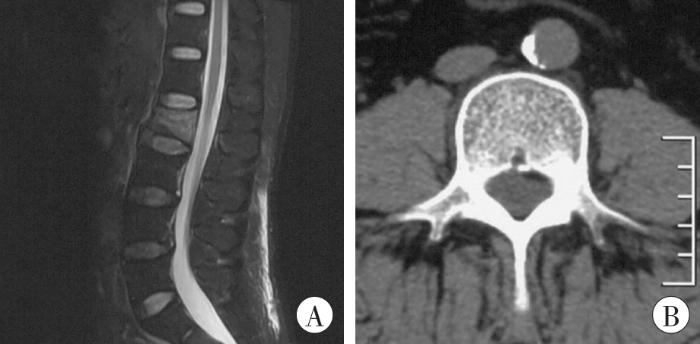

5月13日转入某市人民医院。既往无糖尿病、高血压及感染病史。入院查体:深、浅感觉正常,四肢肌力、肌张力正常,神经生理反射存在,病理反射未引出。腰椎MRI及CT片示:L2椎体压缩性骨折并骨挫伤(骨髓水肿)改变,压缩程度约1/3,骨折累及椎体前、中柱,附件未见确切骨折征象,相应节段椎管未见骨性狭窄,脊髓圆锥未见确切急性损伤信号(图1A);胸主动脉未见明显钙化,腹主动脉管壁钙化(图1B)。入院后完善相关辅助检查:甘油三酯2.10 mmol/L(正常参考值0.45~1.81 mmol/L)、胆固醇7.80 mmol/L(正常参考值2.07~3.10 mmol/L)、低密度脂蛋白5.02 mmol/L(正常参考值2.07~3.10 mmol/L),予匹伐他汀钙片降脂。无绝对手术禁忌证,告知患方保守治疗、切开复位椎弓根螺钉内固定术及有限切开椎弓根螺钉内固定术等治疗方案的优缺点,患方选择有限切开椎弓根螺钉内固定术治疗。于5月17日17:30—19:50在全身麻醉下行“L2椎体爆裂骨折经皮有限切开椎弓根螺钉内固定术”,麻醉用盐酸格拉司琼注射液、盐酸右美托咪定注射液、枸橼酸舒芬太尼注射液、注射用苯磺顺阿曲库铵、丙泊酚乳状注射液、羟乙基淀粉130/0.4氯化钠注射液,吸入医用七氟烷,术中在C臂透视下植入椎弓根螺钉,螺钉位置满意,骨折复位良好,术中失血50 mL。术中血压(16.0~20.0)/(9.3~12.0) kPa[(120~150)/(70~90) mmHg]、呼吸19~20次/min。术后麻醉恢复平稳,血压(16.8~19.2)/(8.3~12.1) kPa[(126~144)/(62~91) mmHg],麻醉苏醒后诉手术切口疼痛,未诉肢体无力等不适。术后约11 h突发右侧胸背部剧烈疼痛,躯体左侧乳头平面以下痛觉、温度觉消失,但触觉、本体感觉正常,左侧提睾反射、肛周反射减弱,左下肢肌力、感觉减退,左侧髂腰肌、股四头肌、胫前肌肌力0级,左侧屈拇趾肌力4级,余各足趾不能屈曲,病理征阴性,膝腱反射、跟腱反射未引出,导尿管通畅,右侧腹壁反射、提睾反射、肛周反射、膝踝反射正常,双上肢及右下肢肌力、肌张力、感觉正常。术后第2天复查全脊髓MRI示:L1~L3椎弓根螺钉内固定术后改变,内固定位置正常,椎管内无异常占位,T3水平以下胸腰段脊髓见散在节段性T1等信号影、T2高信号影,横断面上见T2高信号影位于脊髓偏左侧,颈髓未见异常信号影,胸段及上腰段未见椎间盘突出、椎体骨赘增生等退行性变(图2)。颅脑MRI未见异常。经多学科疑难病例讨论及上级医院远程会诊后考虑脊髓前动脉综合征,予以扩张血管、改善局部微循环、预防血栓、激素抗感染、脱水消肿及营养神经等对症治疗。术后第3天拔除尿管后二便可,术后第6天患者右侧胸背部剧烈疼痛明显缓解,股四头肌肌力1级,左侧髂腰肌、胫前肌肌力0级,左侧屈趾肌力约4级,余持续无明显改善。术后第22天复查甘油三酯2.38 mmol/L、胆固醇7.48 mmol/L、低密度脂蛋白4.53 mmol/L。

图1

图1

术前MRI及CT影像

A:L2椎体压缩性骨折并骨挫伤(骨髓水肿)改变;B:腹主动脉管壁钙化。

Fig. 1

Preoperative MRI and CT images